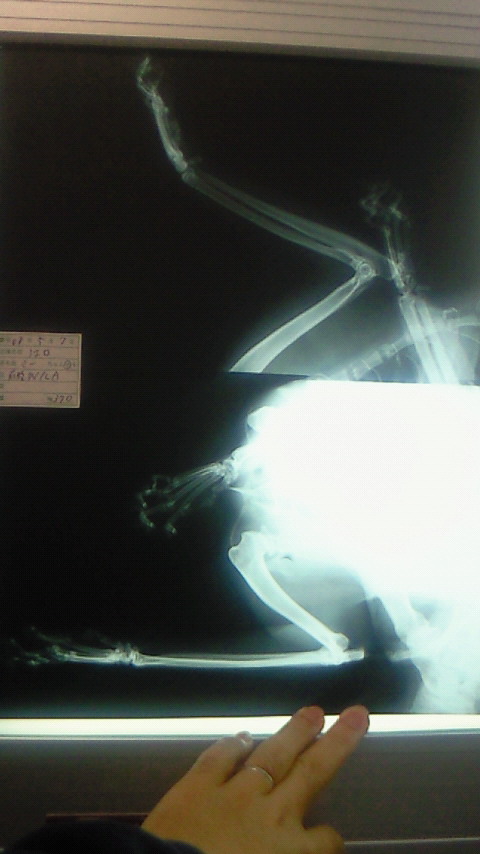

まずはレントゲンとって骨に異常がないかチェック。

これがみぃちゃんの前足付近のレントゲン映像。

骨がほそーい!